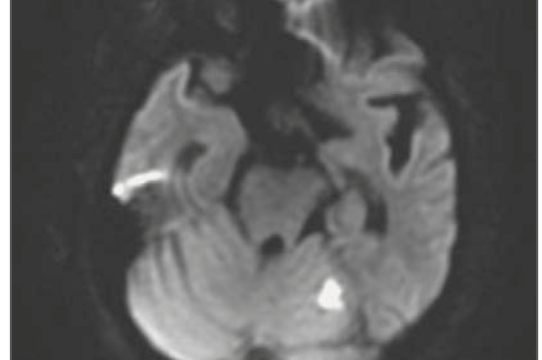

クリプトコッカス髄膜炎